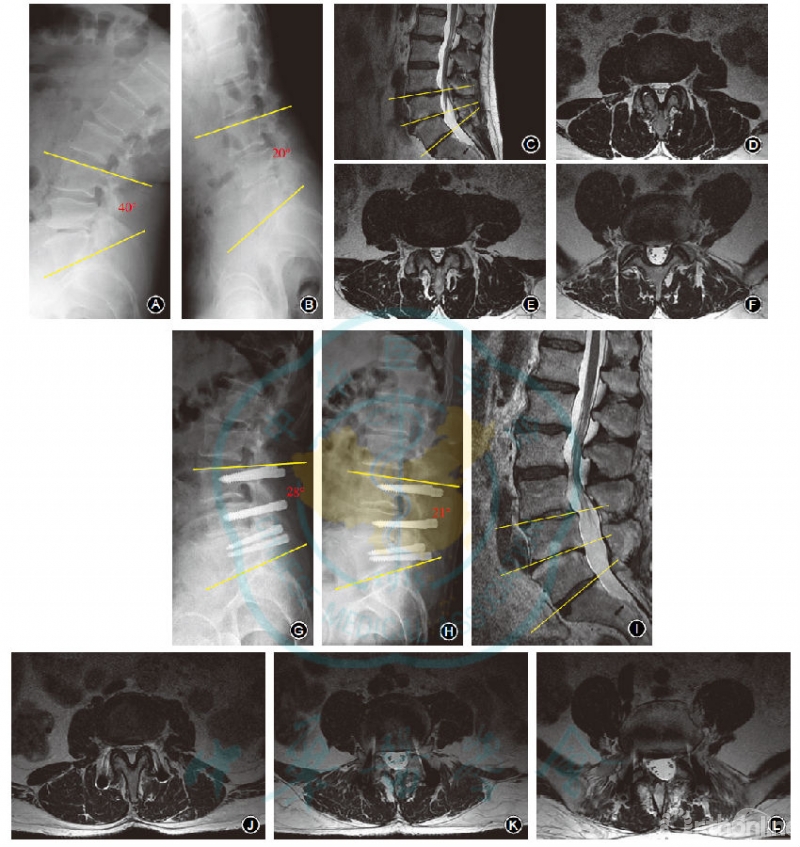

术前Dynesys组颅侧邻近节段ROM为8.5°±1.7°,PLIF组为8.7°±2.1°,末次随访时Dynesys组为10.5°±2.3°,PLIF组为13.6°±3.4°,分别均较术前增加,差异均有统计学意义(均P<0.05);且组间差异有统计学意义(t=4.834,P<0.05,图2)。

图2 男,56岁,腰椎间盘突出症,腰椎管狭窄症,行L3~L5 Dynesys动态内固定手术治疗A,B 术前腰椎过伸过屈位X线片示L3~L5节段轻度不稳,手术节段ROM为20° C~F 术前腰椎MR检查T2WI示L3-4、L4-5椎间盘突出伴椎管狭窄G,H 术后1.5年腰椎过伸过屈位X线片示腰椎内固定固定在位,腰椎曲线良好,手术节段ROM为7° I~L 术后7年腰椎MR检查T2WI示L3,4、L4,5椎间隙高度较术前稍有所丢失,椎管狭窄程度较前未明显增加